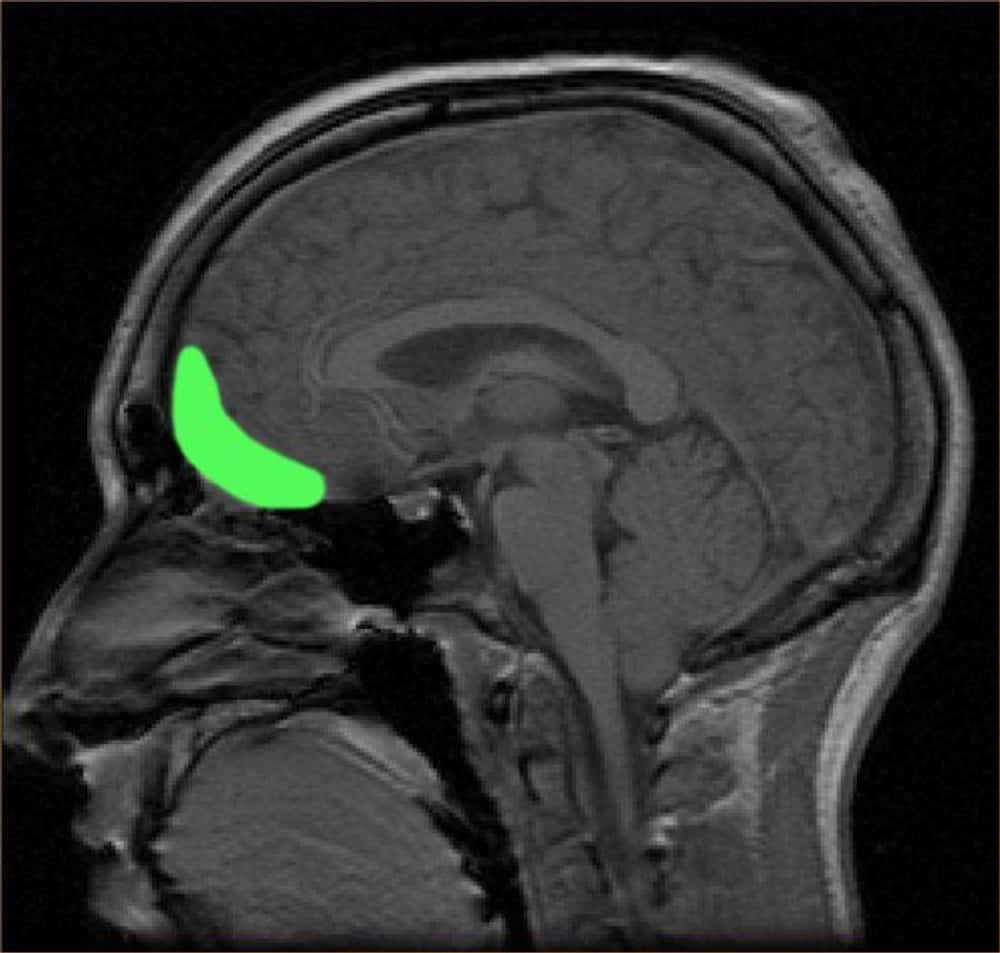

Az álmok gyakran nem állnak össze, és ennek van oka. Alvás közben az agy több területe gyengébben kommunikál egymással. Különösen a frontális lebeny húzódik vissza, amely a tudatosságért és a logikus döntésekért felel.

A frontális lebeny inaktivitása miatt hozunk rossz döntéseket az álmainkban. A valóságban e terület sérülése vagy gyenge működése erőszakosságot, depressziót vagy demenciát is okozhat, ezért jobb, ha ez a visszafogottság csak alváskor jelentkezik.